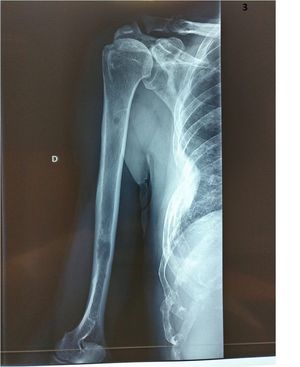

Radiology

Radius